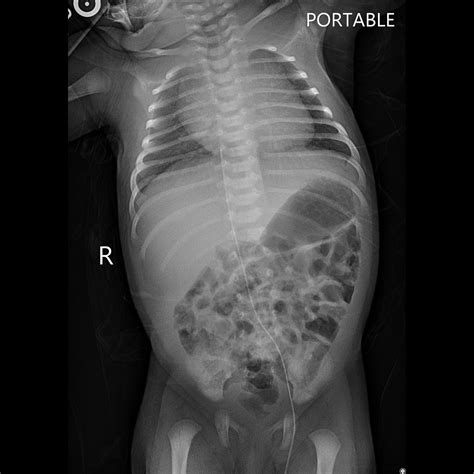

• Assessment of Congenital Anomalies: X-rays can help identify congenital anomalies, such as heart defects or skeletal abnormalities, which may require immediate medical attention.

Congenital Anomalies X-rays can reveal congenital anomalies, such as heart defects or skeletal abnormalities, which may require immediate medical attention.

• Radiologist Review: The X-ray images are reviewed by a radiologist, who will look for any signs of fractures, infections, or other abnormalities.